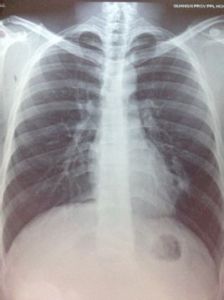

示意圖患者一旦發現肺部陰影可不必過度緊張,而應該積極找專科醫生(胸外科、呼吸內科)明確診斷,醫生會根據患者的具體情況套用其它的輔助檢查手段,如胸部CT、纖維支氣管鏡、CT定位下穿刺、痰細胞檢查等進一步明確診斷。一旦診斷明確,醫生就會制定出正確的治療方案。

肺部陰影跟肺癌並不能劃等號,很多病在胸片上都可能有如此表現,關鍵是要鑑別清楚。一般來說,引起“肺部陰影”的疾病主要有三類。

第一類是肺部感染性疾病,包括肺炎、肺結核、支氣管擴張、肺麴黴菌病等。肺炎指的是細菌、支原體、衣原體、病毒等引起的肺部感染,除了X線檢查有肺部陰影外,患者還有咳嗽、咳痰、發燒、胸悶、乏力、呼吸困難等症狀,嚴重者可能發生感染中毒性休克。細菌導致的肺炎最常見,陰影在X光胸片上往往呈片狀。套用抗生素治療後複查胸片,可以發現肺部陰影明顯縮小,甚至完全消失,一般治療2周即可痊癒。

肺結核是結核桿菌造成的肺部感染,近年來發病率有增多趨勢。胸片上的肺部陰影往往表現為散在的片絮狀,當中可有鈣化灶,看上去就像是白點。患者常有咳嗽、咳痰和咳血以及午後低熱、乏力、盜汗、食慾減退等結核中毒症狀。如果在痰液里查到抗酸桿菌,皮膚結核菌素試驗呈強陽性,就可以明確診斷。多數肺結核患者套用抗結核藥物(雷米封、利福平、乙胺丁醇等)治療效果良好,病情嚴重的則須手術治療。

有的病人肺部陰影呈蜂窩狀,如果長期咳膿痰、咳血,就要懷疑支氣管擴張的可能。支氣管擴張是支氣管壁化膿性感染造成的支氣管腔擴大,胸片往往表現為肺紋理增多、增粗、紊亂。以往支氣管碘油造影是診斷支氣管擴張的金標準,目前螺鏇CT可以進行無任何創傷的支氣管形態重建,能夠明確診斷。如果病灶局限於1—2個肺葉,且全身情況良好,應該積極手術治療,但如果是雙側廣泛的病灶就不宜手術。

引起“肺部陰影”的第二類疾病就是肺部腫瘤。不過,肺部腫瘤不等於肺癌,更不等於不治之症。對“肺部陰影”的恐慌主要來自肺癌。此病好發於中老年人,肺部陰影多為球形,仔細觀察其邊緣呈分葉狀,有的患者的陰影邊緣有“毛刺”,有的病人則表現為與肺炎類似的片狀陰影。一般來說患者會出現刺激性咳嗽、血痰、胸痛、消瘦、聲音嘶啞、飲水嗆咳等症狀。胸部CT檢查、痰化驗、纖維支氣管鏡檢查或CT定位下穿刺活體組織檢查可以明確診斷。

如果身體其他部位的惡性腫瘤轉移到肺部,這就是肺部轉移癌。這種肺部陰影常常表現為單個或多個圓形陰影,呈毛玻璃樣,邊界清晰,多位於雙肺的外側。患者多數沒有症狀,這時應該積極尋找原發病灶,在原發病灶去除後,可以手術切除單發的肺部轉移灶。

如果肺部感染治療後病灶沒有完全吸收,有可能形成肺炎性假瘤。多數患者有以往的肺炎病史,發現肺部陰影時多數沒有任何症狀。

除了上述疾病,肺部先天性發育異常也可以導致肺部陰影,但一般比較少見,如肺囊腫、肺錯構瘤、肺隔離症等。肺囊腫多發生於男性兒童和青壯年,X線胸片特點為單個或多個圓形薄壁陰影,邊緣清楚,如果囊腫和支氣管相通,就會在陰影中發現氣液平面。

肺錯構瘤的典型胸片表現為“爆米花樣”。肺隔離症是先天性的肺發育異常,肺部陰影多呈不規則的三角形、多邊形、圓形或橢圓形,邊緣銳利,密度均勻。 由此可見,許多良性疾病也會表現為“肺部陰影”。有了“肺部陰影”,患者應積極到胸外科、呼吸內科就診明確診斷。只有診斷明確,才能制訂出正確的治療方案。